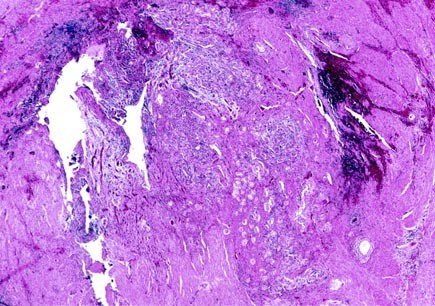

FIGURE 2

Cross-section of ureter. Its lumen is almost completely obliterated by nephrogenic metaplasia, inflammatory cells, and fibrosis.